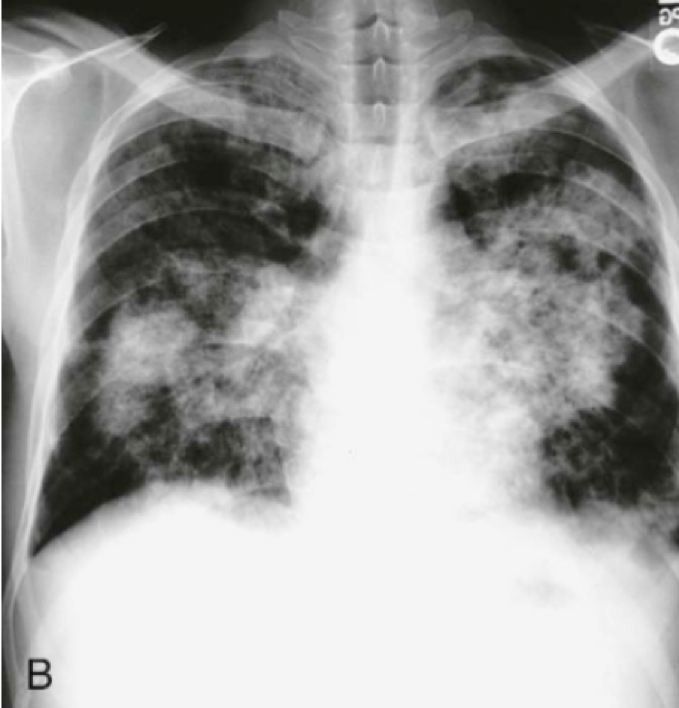

Question 12

Question

In what disease will you see this in?

Answer

• Pneumocystis jiroveci

• Kaposi’s Sarcoma

• Tuberculosis (TB)

• Silicosis